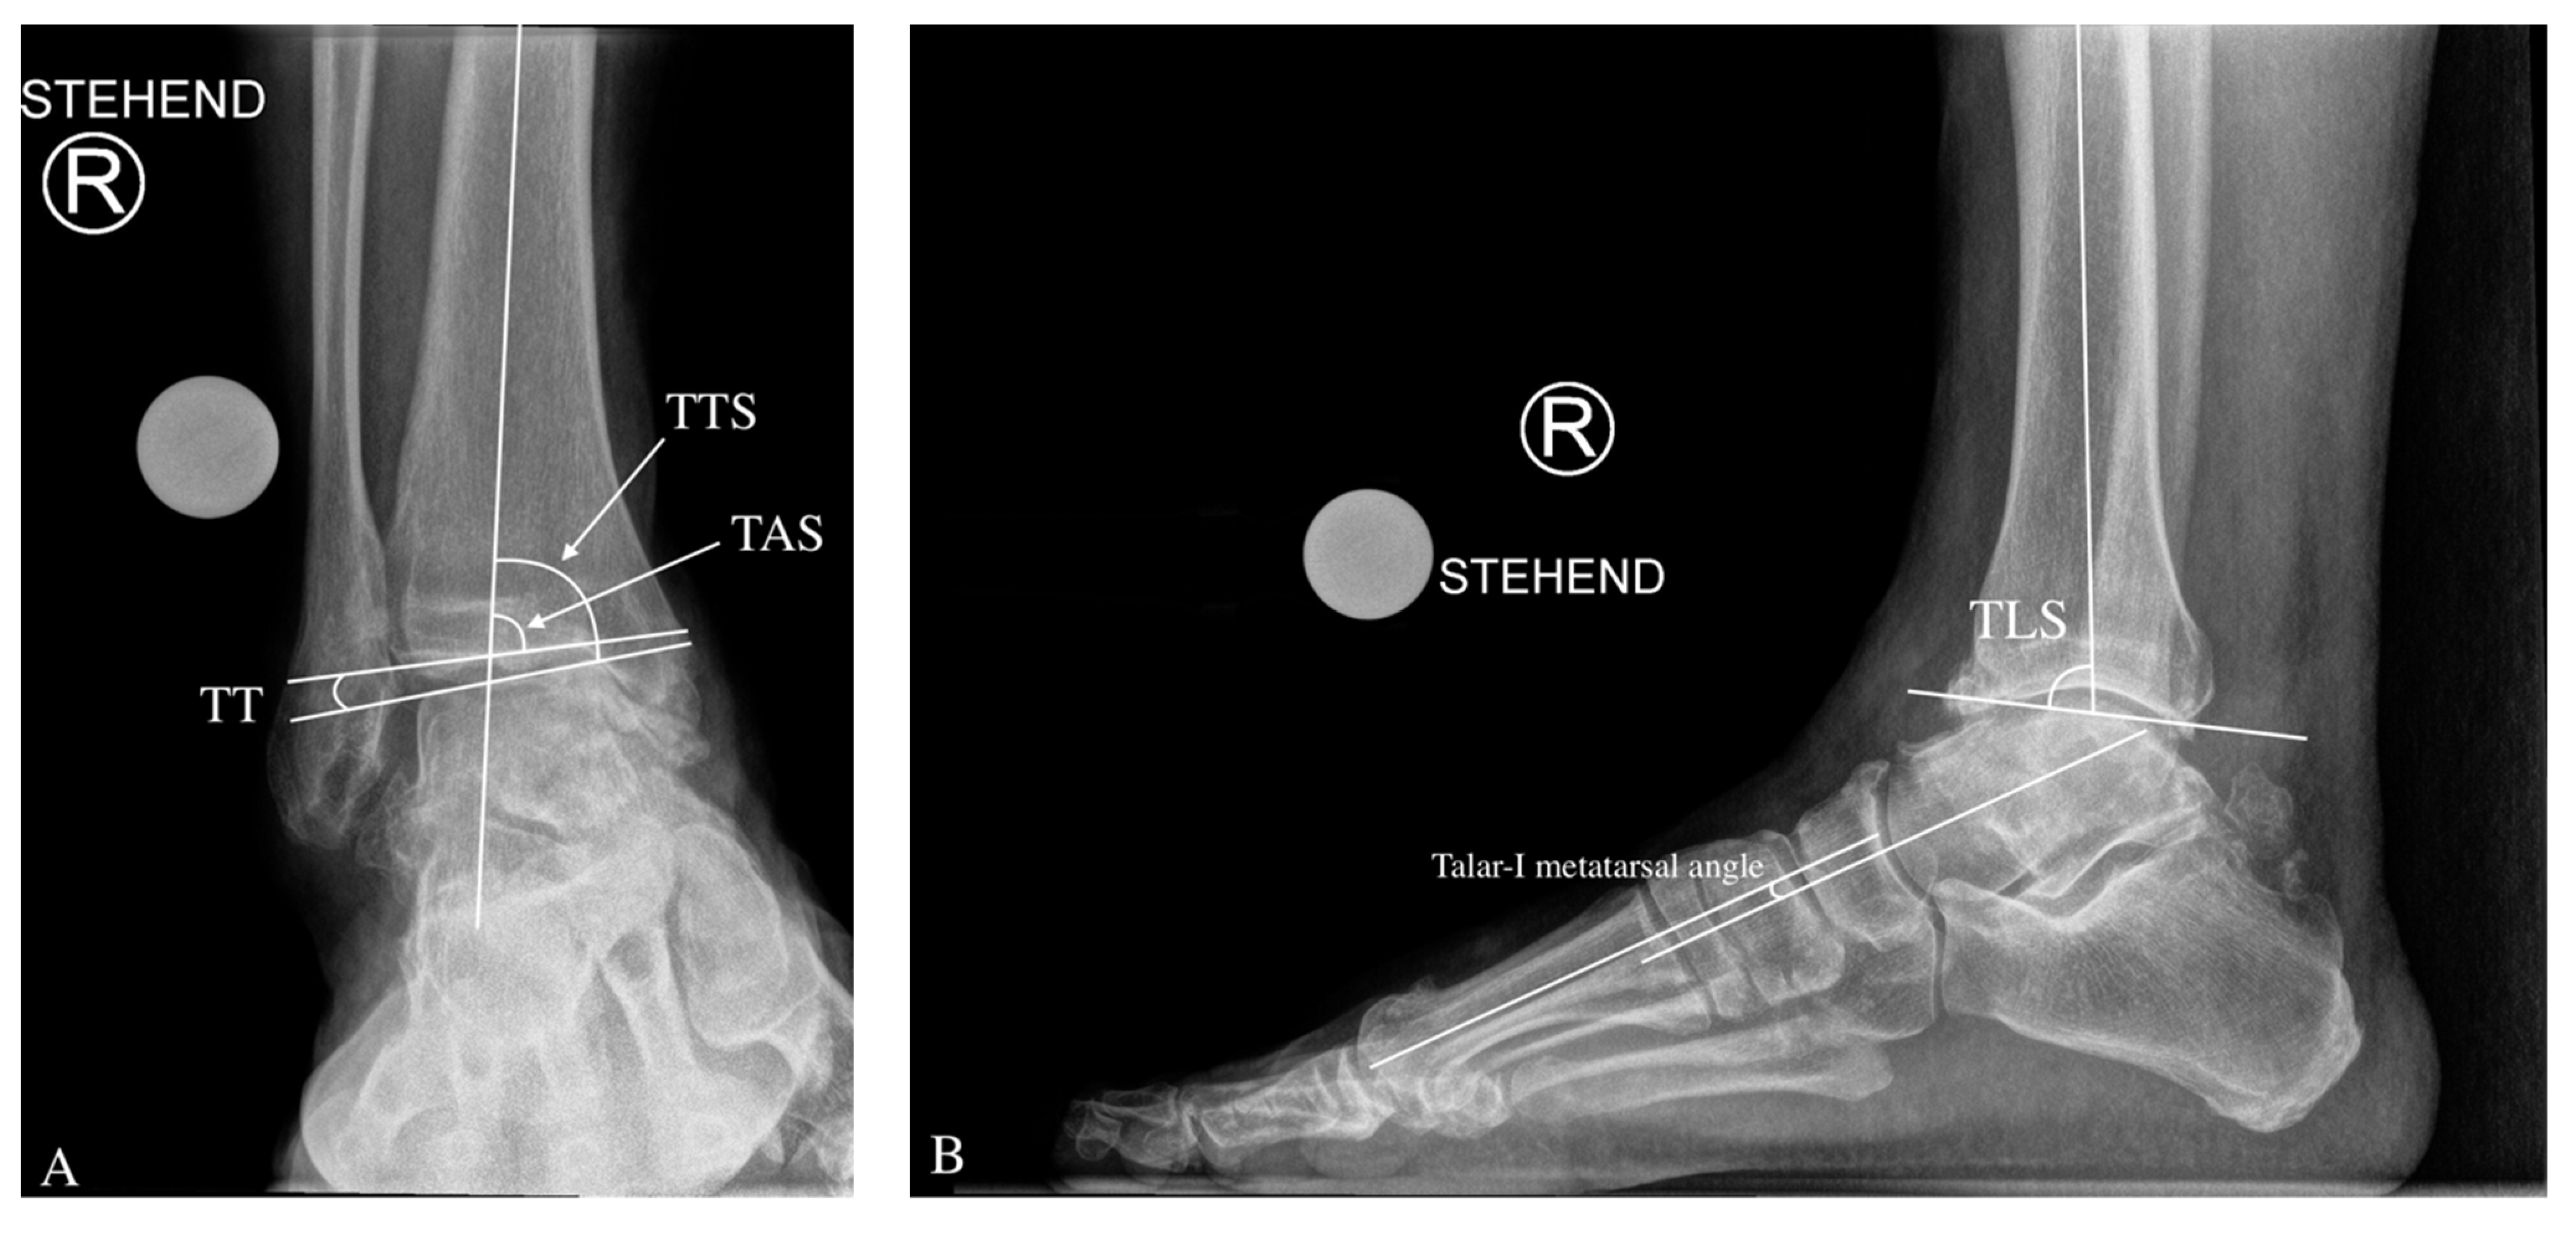

3.2. Preoperative Radiological Angle Measurements